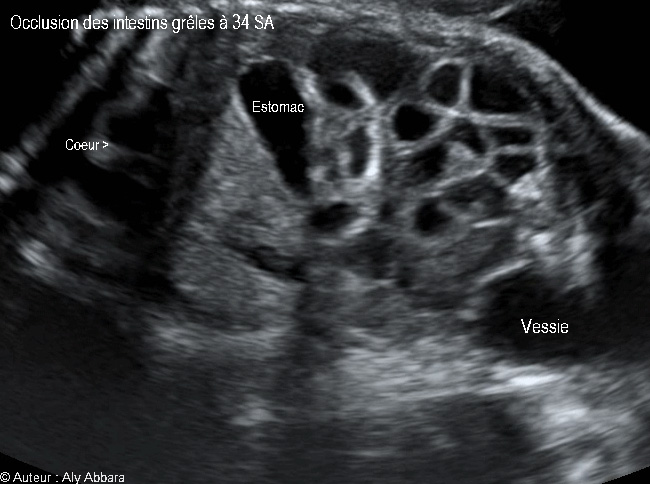

Images échographiques montrant une occlusion intestinale se manifestant par la dilatation des anses grêles et un hyperpéristaltisme.

Cette occlusion intestinale est liée à la présence, dans la fosse iliaque droite, d'un magma d'anses grêles hyperdenses, agglutinées et obstruées.

L'estomac n'est pas dilaté (occlusion digestive basse), mais on note également l’existence de deux anomalies morphologiques associées :

* Une agénésie du rein droit

* L'absence, au niveau de crosse de l'aorte, de sa 3ème branche, c'est-à-dire l'artère subclavière gauche.

Il s'agit d'une fœtus de 34 SA ; après sa naissance à 38 SA, cette occlusion des anses grêles a nécessité deux interventions chirurgicales digestives dans la période néonatale.